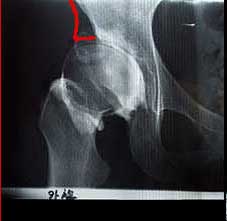

私の右股関節レントゲンです。

(造影剤を使用したX線なので少し白く濁っています)

通常の股関節は赤い線のあたりまでかぶりがあります。

私の股関節はこのかぶりが小さいことから、足に余計な負担がかかってしまうようです。

このまま放置して進行すると、間接の部分が破壊される恐れがあります。